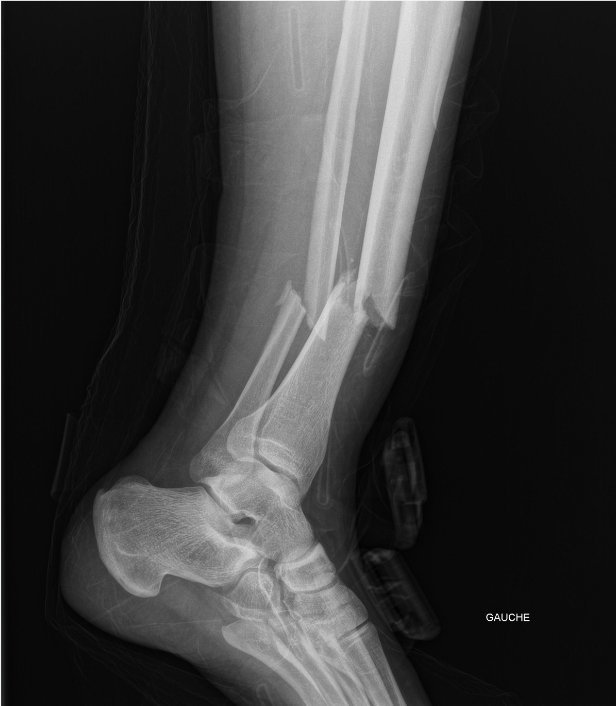

Double fracture du tibia péroné, des questions ?

Je me suis fait ça aujourd'hui dans l'aprèm

chute en moto

la moto qui tombe pleinement sur la jambe gauche

Accident en moto à la con, j'ai mal négocié un virage en descente et j'ai freiné trop fort, j'ai basculé par dessus la moto et elle m'a écrasé la jambe.

La jambe bien droite, la pente + la moto de 300kg qui tombe dessus, ça pardonne pas :)